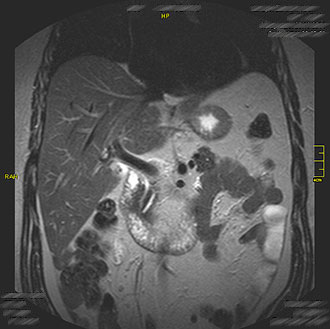

Die MRT Bauch bietet die Möglichkeit, Organe wie Leber, Bauchspeicheldrüse, Nieren oder Gefäße strahlungsfrei darzustellen. Unsere Praxis in Köln setzt auf modernste MRT-Technik, um Erkrankungen des Bauchraumes präzise zu erkennen.

Die Untersuchung wird häufig bei unklaren Bauchschmerzen, Tumorverdacht, Entzündungen oder Gefäßerkrankungen durchgeführt. Dank hoher Auflösung lassen sich auch kleine Veränderungen zuverlässig darstellen.

Die MRT des Bauches (Abdomen-MRT) ist ein hochauflösendes, strahlungsfreies Verfahren zur Beurteilung der inneren Organe.

Im Kernspin Zentrum Köln werden mit modernster Magnetresonanztomographie (MRT) Leber, Gallenwege, Milz, Bauchspeicheldrüse, Nieren und Nebennieren detailliert dargestellt.

Die Untersuchung ermöglicht eine frühzeitige Erkennung von Entzündungen, Tumoren oder strukturellen Veränderungen – für eine sichere und gezielte Diagnostik.

Die MRT der Leber ist eines der wichtigsten Verfahren in der Abdominaldiagnostik. Sie erlaubt eine präzise Beurteilung von Lebertumoren, Leberzysten, Läsionen, Hepatitis und Leberzirrhose.

Im Kernspin Zentrum Köln kann mit Hilfe spezieller MRT-Sequenzen die Gewebestruktur der Leber sehr genau analysiert werden – ideal zur Differenzierung zwischen gutartigen und bösartigen Veränderungen.

Gerade bei unklaren Befunden aus Ultraschall oder CT bietet die MRT entscheidende Zusatzinformationen.